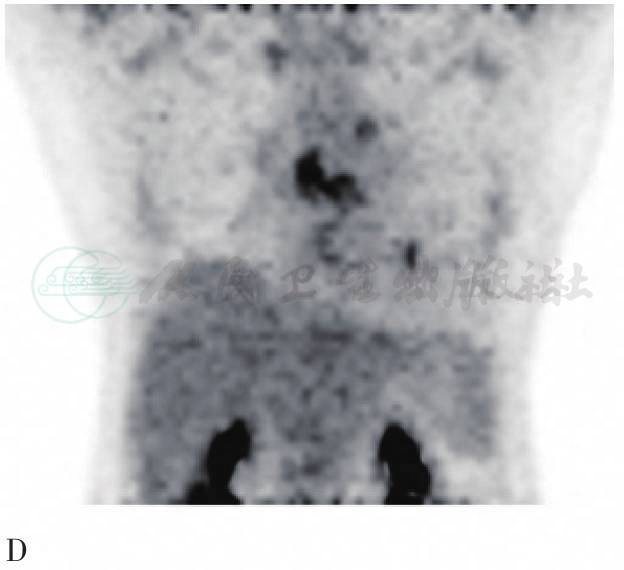

图1 PET/CT图像

A. 心脏CT横断面;B. 心脏PET横断面;C. 心脏PET/CT横断面融合图像;D. 胸部PET MIP图。PET见右室流出道不规则团状异常显像剂浓聚灶(粗黄色箭头)SUVmax约为6.9;CT相应部位见不规则软组织密度影(粗白色箭头)。CT心脏壁层心包增厚(细白箭头),最厚约为11.9mm,心包腔内见液体密度影;PET未见异常显像剂浓聚影